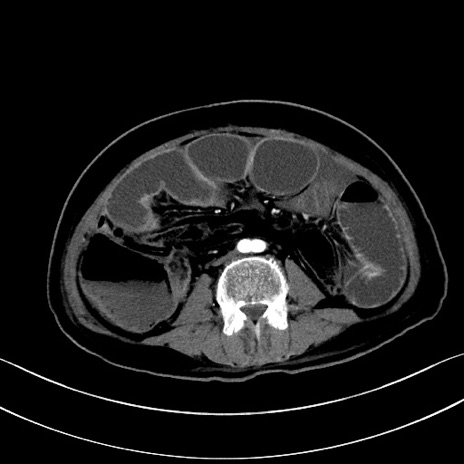

症例28(横断像)

【症例】60歳代男性

【主訴】嘔吐

【現病歴】胃癌にて胃全摘後。食思不振が悪化し、夜中に嘔吐することがある。

【既往歴】胃癌、胃全摘、脾摘、胆摘後

【データ】WBC 5900、CRP 10.56